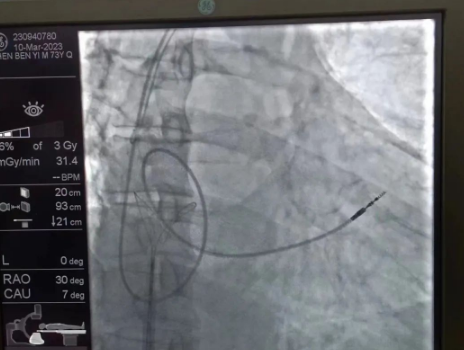

“成功拔除心臟起搏電極。”心臟DSA手術(shù)室外,觀摩手術(shù)的醫(yī)生中爆發(fā)出一陣熱烈的掌聲。3月10日,西安國際醫(yī)學(xué)中心醫(yī)院心臟病醫(yī)院副院長李偉杰教授為一名老年男性患者成功拔除了斷裂的心臟起搏電極,并為患者植入新的起搏電極。

術(shù)中,孫書紅醫(yī)師首先切開起搏器囊袋,游離出起搏器脈沖發(fā)生器,發(fā)現(xiàn)起搏電極完全斷裂,連接于起搏脈沖發(fā)生器,殘端約10cm;考慮患者為起搏依賴患者,需再次植入新的起搏電極導(dǎo)線,穿刺了腋靜脈,放置導(dǎo)絲;同時,李偉杰教授穿刺了左、右股靜脈,于右股靜脈置入了”抓捕器”,左股靜脈備用臨時起搏通路,以防術(shù)中出現(xiàn)心跳驟停。為了準確抓捕到心房內(nèi)的在逃起搏電極,李偉杰教授將導(dǎo)管室的X光機球管調(diào)整成了冠脈模式,這就意味著在抓捕過程中,醫(yī)生要比平時的手術(shù)“吃”更多射線……

在透視模式下,抓捕全憑醫(yī)生的經(jīng)驗與手感,一次次嘗試,一次次失敗,在場外觀摩手術(shù)的醫(yī)生同樣為李偉杰教授捏了一把汗,“找到了!”電子屏里抓捕器向在逃起搏電極“發(fā)起進攻”,一把逮住并順利拔出一根長達58cm的起搏電極。